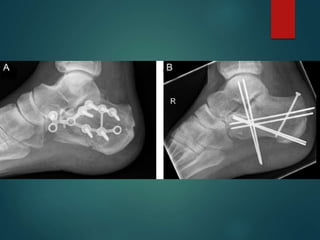

Calcaneal Fractures

 Falling from height can lead to severe calcaneal

fractures, which may be accompanied by axial loading

fractures of the spine.

▪

▪ Calcaneal fractures due to a fall from height are often

comminuted and intra-articular.

Types of calcaneal

fractures

 Intra and Extrarticular fractures on the basis of subtalar

joint involvement.

▪ Intrarticular fractures are more common and

involve the posterior talar articular facet of the

calcaneus.

▪ Extrarticular fractures are less common, and

located anywhere outside the subtalar joint.

The Sanders system classification

Is the most commonly used system for categorizing

intrarticular fractures.

Classifies these fractures into four types, based on the location

of the fracture at the posterior articular surface.

TYPES

▪ Type I fractures are non-displaced fractures (displacement <

2 mm).

▪ Type II fractures consist of a single intrarticular fracture that

divides the calcaneus into 2 pieces.

▪ Type III fractures consist of two intrarticular fractures that

divide the calcaneus into 3 articular pieces.

▪ Type IV fractures consist of fractures with more than three